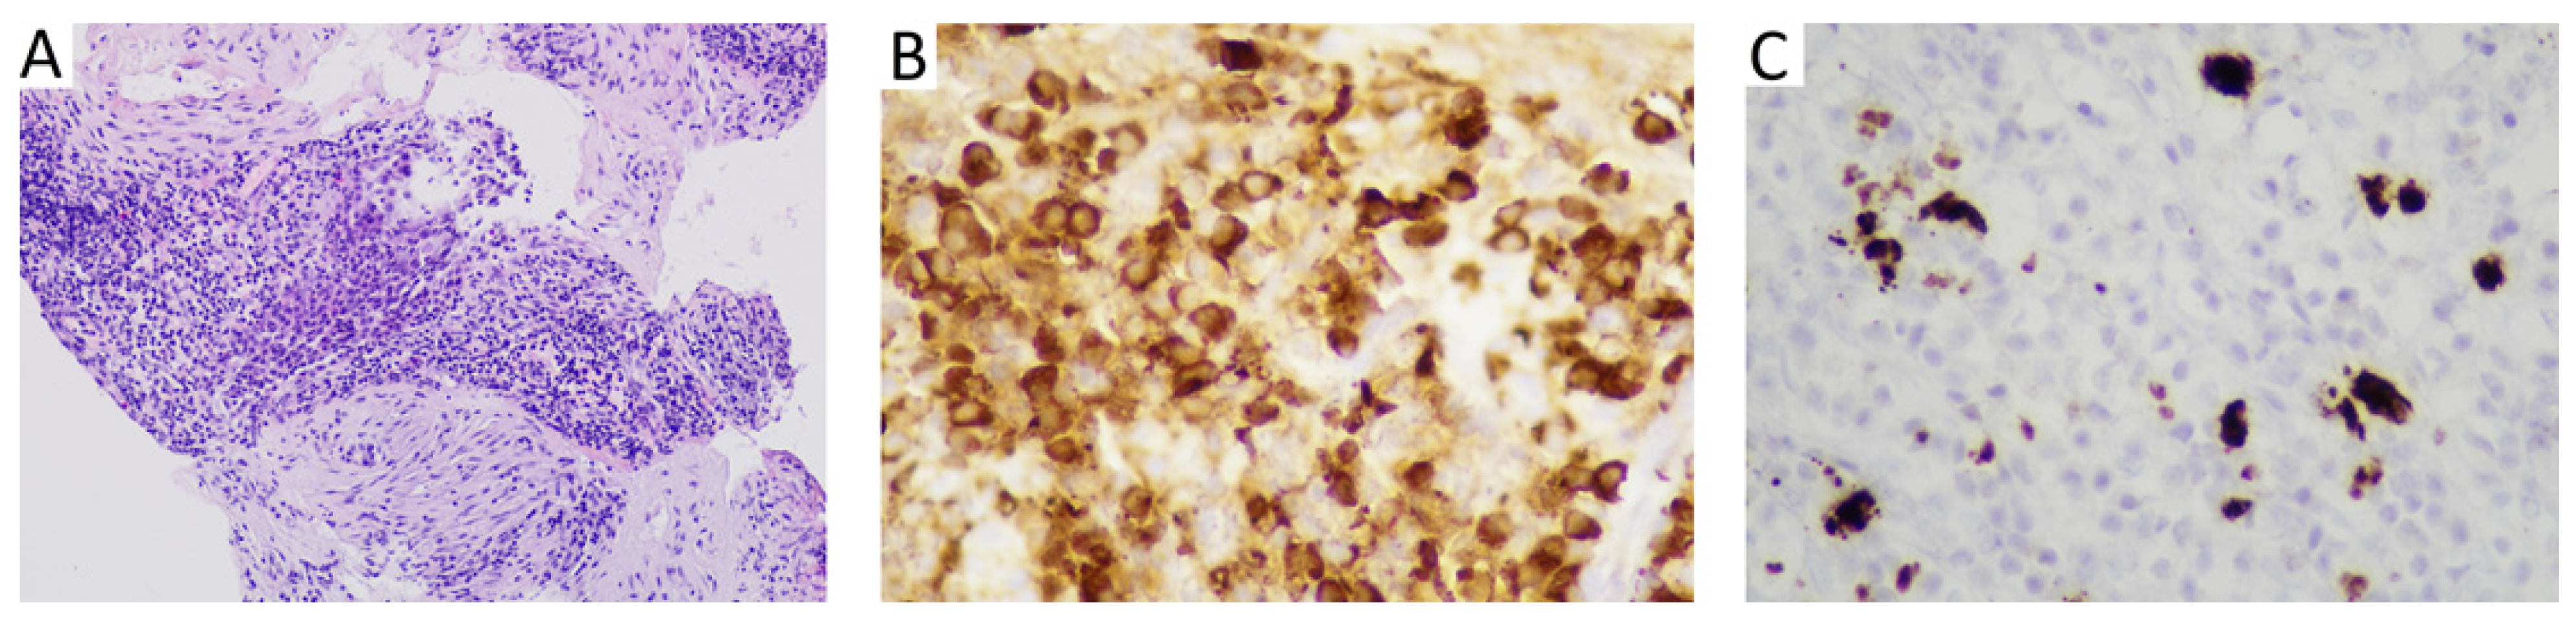

3.2. Case 2

| 19 | 2021 | Israel | Present study | 44 | m | otitis media | 1 | - | fibrous tissue, dense lymphoplasmacytic inflammation, storiform fibrosis | IgG4 25 per HPF; IgG4:IgG < 20% | Data not available |